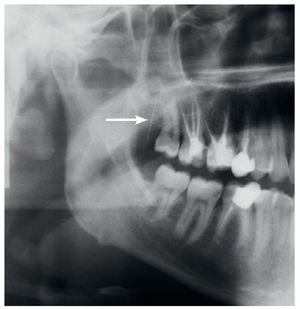

Un paciente de 35 años de edad acudió a la consulta de su odontólogo de cabecera por un cuadro de dolor agudo en el lado derecho de la mandíbula. La punta de la aguja se rompió durante la anestesia de conducción del nervio dentario inferior. No fue posible localizarla desde la cavidad oral. El paciente fue remitido para su diagnóstico y tratamiento urgente a la Clínica de Cirugía Maxilofacial de la Clínica Universitaria de Zúrich. Una ortopantomografía obtenida por el odontólogo de cabecera evidenciaba claramente la punta rota en proyección sobre la tuberosidad maxilar derecha (fig. 1). A su llegada a la clínica el paciente estaba asintomático. En la exploración clínica no se logró localizar con precisión la aguja. Se practicó una tomografía computarizada para una evaluación exacta. En la TC se observó la aguja rota en la zona del tejido adiposo y la cara inferior del músculo masetero directamente en medial del arco cigomático y en la parte anterior de la rama ascendente de la mandíbula (fig. 2).

Figura 1. En la ortopantomografía realizada por el odontólogo de cabecera se observa una imagen radioopaca de densidad metálica de 20 mm de largo que se proyecta sobre la tuberosidad maxilar derecha.

Se informó al paciente del diagnóstico y de la intervención prevista con anestesia general para la extracción de la aguja. Se practicó una incisión intraoral (fig. 3a) sobre la rama ascendente que no planteó problemas. Con ayuda de la fluoroscopia dinámica y una pinza mosquito como referencia se consiguió localizar rápidamente la punta de la aguja rota. A continuación, se consiguió sujetarla y extraerla sin contratiempos (fig. 3b). Se trataba de una aguja para inyección de calibre 30 y de 25 mm de largo (fig. 3c). El periodo postoperatorio transcurrió sin complicaciones.

Figura 3c. Punta de aguja rota comparada con una aguja para inyección de dimensiones idénticas y con una aguja adecuada para la anestesia de conducción del nervio dentario inferior (35 mm, calibre 27).